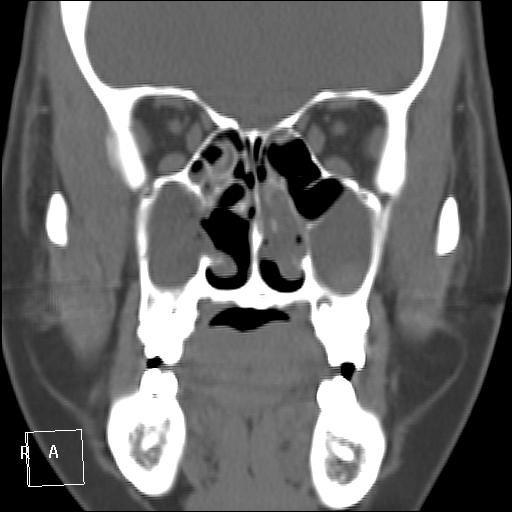

КТ ППН и носоглотки. Девушка 21 года. Полипозный риносинусит.

Госпитализирована для оперативного лечения. Удалены полипы носа. Вторым этапом планируется гайморотомия. Во время операции - подозрение на образование носоглотки. Сохраняется затруднение носового дыхания. Направлена на КТ. Категорически отказалась от контрастировния (лекарственная полиаллергия, боится).

Полип в носоглотке справа. Нарушена пневматизация придаточных пазух носа кроме левой решётчатой. В левой гайморовой на дне неясно что…

На дне гайморовой - полип, в носоглотке немаленький хоанальный полип. Там всё в полипах, а они и фиброзные бывают, и ангиофибромы, и ангиоаденомы... Вот и плотность разная.

Ну, как-то все в одну кучу - и полипы, и ангиофибромы. При ангиофиброме, например, околоносовые пазухи свободны. А гиперденсность более характерна для грибкового поражения (аспергилеза), в том числе и "севшим" на пломбировочный материал.

На операции визуально полипы аденоматозного типа. Какие будут гистологически после гайморотомии - сейчас трудно сказать. Если б гиперденсность была только по нижней стенке верхнечелюстной пазухи, тогда вариант с аспергиллезом на пломбировочном материале, на мой взгляд, был бы более вероятен. У девушки участки гиперденсности по всем стенкам верхнечелюстных пазух, в основной пазухе, совсем чуть - в решетчатом лабиринте слева, без костной деструкции. Без посева и гистологии - только гадать)). В носовой полости признаков грибкового поражения ЛОРы не отмечают. Но Вы правы, может иметь место изолированное поражение синусов.